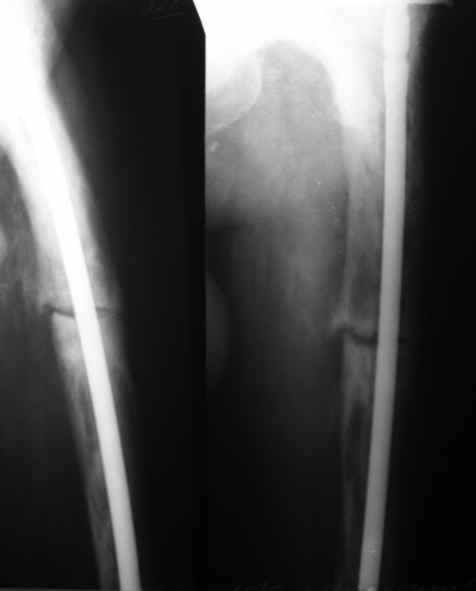

Пациент 82 лет, поступил через 5 мес. с несросшимся переломом после открытого интрамедуллярного остеосинтеза. Выполнили реостеосинтез стержнем 12 мм. ( мах. доступного нам в 2003 г.) Через 4 мес динамизация. В течении 2х лет сращения нет, тем не менее конечность опорна (ходит с тростью). От очередного реостеосинтеза отказались из-за сопутств. патологии.